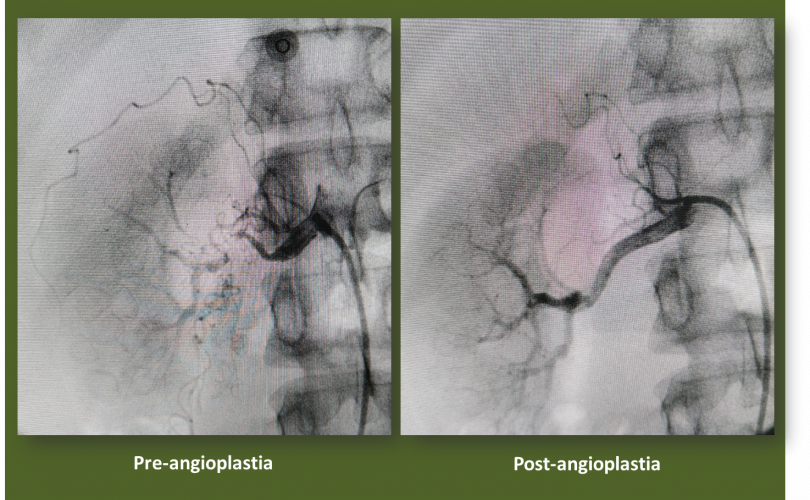

Las técnicas de diagnóstico por imagen utilizadas preferentemente son la ecografía doppler, la tomografía computerizada y la resonancia magnética. La Arteriografía por Sustracción Digital (ASD) es la exploración diagnóstica que confirma la estenosis o obstrucción, y es el paso previo al tratamiento endovascular percutáneo.

El tratamiento tiene el objetivo de recuperar el calibre de la arteria renal, mediante diferentes técnicas de revascularización. Estas pueden ser percutáneas o quirúrgicas. En la estenosis de la arteria renal, la primera opción de tratamiento es la revascularización por vía percutánea.